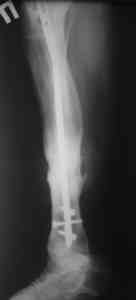

Пример (пациент 46 лет, лечился у нас 4 года назад, внутренний остеосинтез выполнен с определенными погрешностями, но перелом сросся и рецидива инфекции не было): рис. 1,2 - при переводе к нам в институт, рис. 3 - после микрохирругической пластики, рис. 4, 5 - после интрамедуллярного остеосинтеза, рис. 6, 7, 8 - внешний вид и рентгенограммы после окончания лечения

Больному была выполнена операция. после демонтажа аппарата Илизарова столкнулись с "прямо на глазах" сокращением регенерата. Гвоздь сквозь регенерат удалось провести без технических трудностей. Сложности были с репозицией отломков, что связано с выраженным остеопорозом, их короткими размерами. Пришлось применить полер-винт. Выполнили блокирование. По причине укорочения регенерата пришлось повторно смонтировать аппарат Илизарова и начать транспорт фрагмента на гвозде (14 мм). Больному разрешена ходьба с дозированной нагрузкой на больную ногу. Контрольные рентгенограммы прилагаются. Нынешняя ситуация породила ряд вопросов и замечаний:

1)Как долго удерживать аппарат без риска повторного укорочения регенерата?

2)Когда можно будет разрешить полную нагрузку на больную конечность?